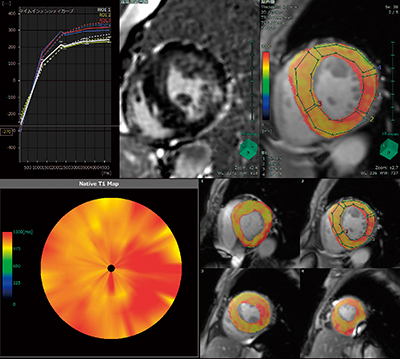

上記の背景を踏まえ,最新のバージョンでは,心筋領域に対しピクセルごとにT1値を計算する“心筋TxMap”アプリケーションをリリースした(図3)。

modified look-locker inversion recovery法で撮像された画像を用いて,すべてのピクセルを対象に,異なるinversion timeごとのsignal intensityから作成されたtime intensity curveを基に近似曲線を求め,これを縦緩和時間の曲線としてT1値を推定する。

非造影MR画像から計算したT1値をNative T1Map,造影MR画像から計算したT1値をT1Mapと呼んでいる。一般的に造影前後のMR画像を用いて診断結果として用いることが多いが,造影剤投与が禁忌なケースも考慮し,非造影MR画像のみからT1値を計算できるようになっている。

図3 心筋TxMapの解析結果画像例

NativeT1Map,T1Mapに遅延造影画像を同時に比較表示できる

レイアウトも用意している。